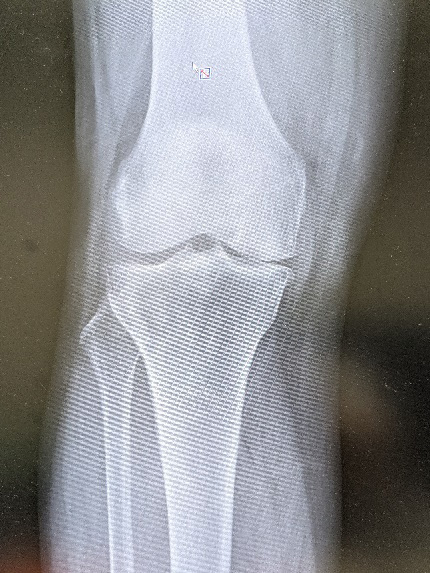

人工膝関節置換術

膝関節の軟骨のすり減りや骨の変形により歩行時の痛みが強い場合に行う手術で、膝の痛んでいる部分を切除し金属に置き替える手術です 痛みの軽減と歩行能力の改善には大きな効果があります 変形が進行し、強い痛みのため日常生活に支障が出ている方に適した治療法です。

高度な変形やリウマチなどに対しは全人工膝関節置換術(TKA)を行います。痛みが膝の内側か外側だけの場合には単顆部膝関節置換術(UKA)行います。